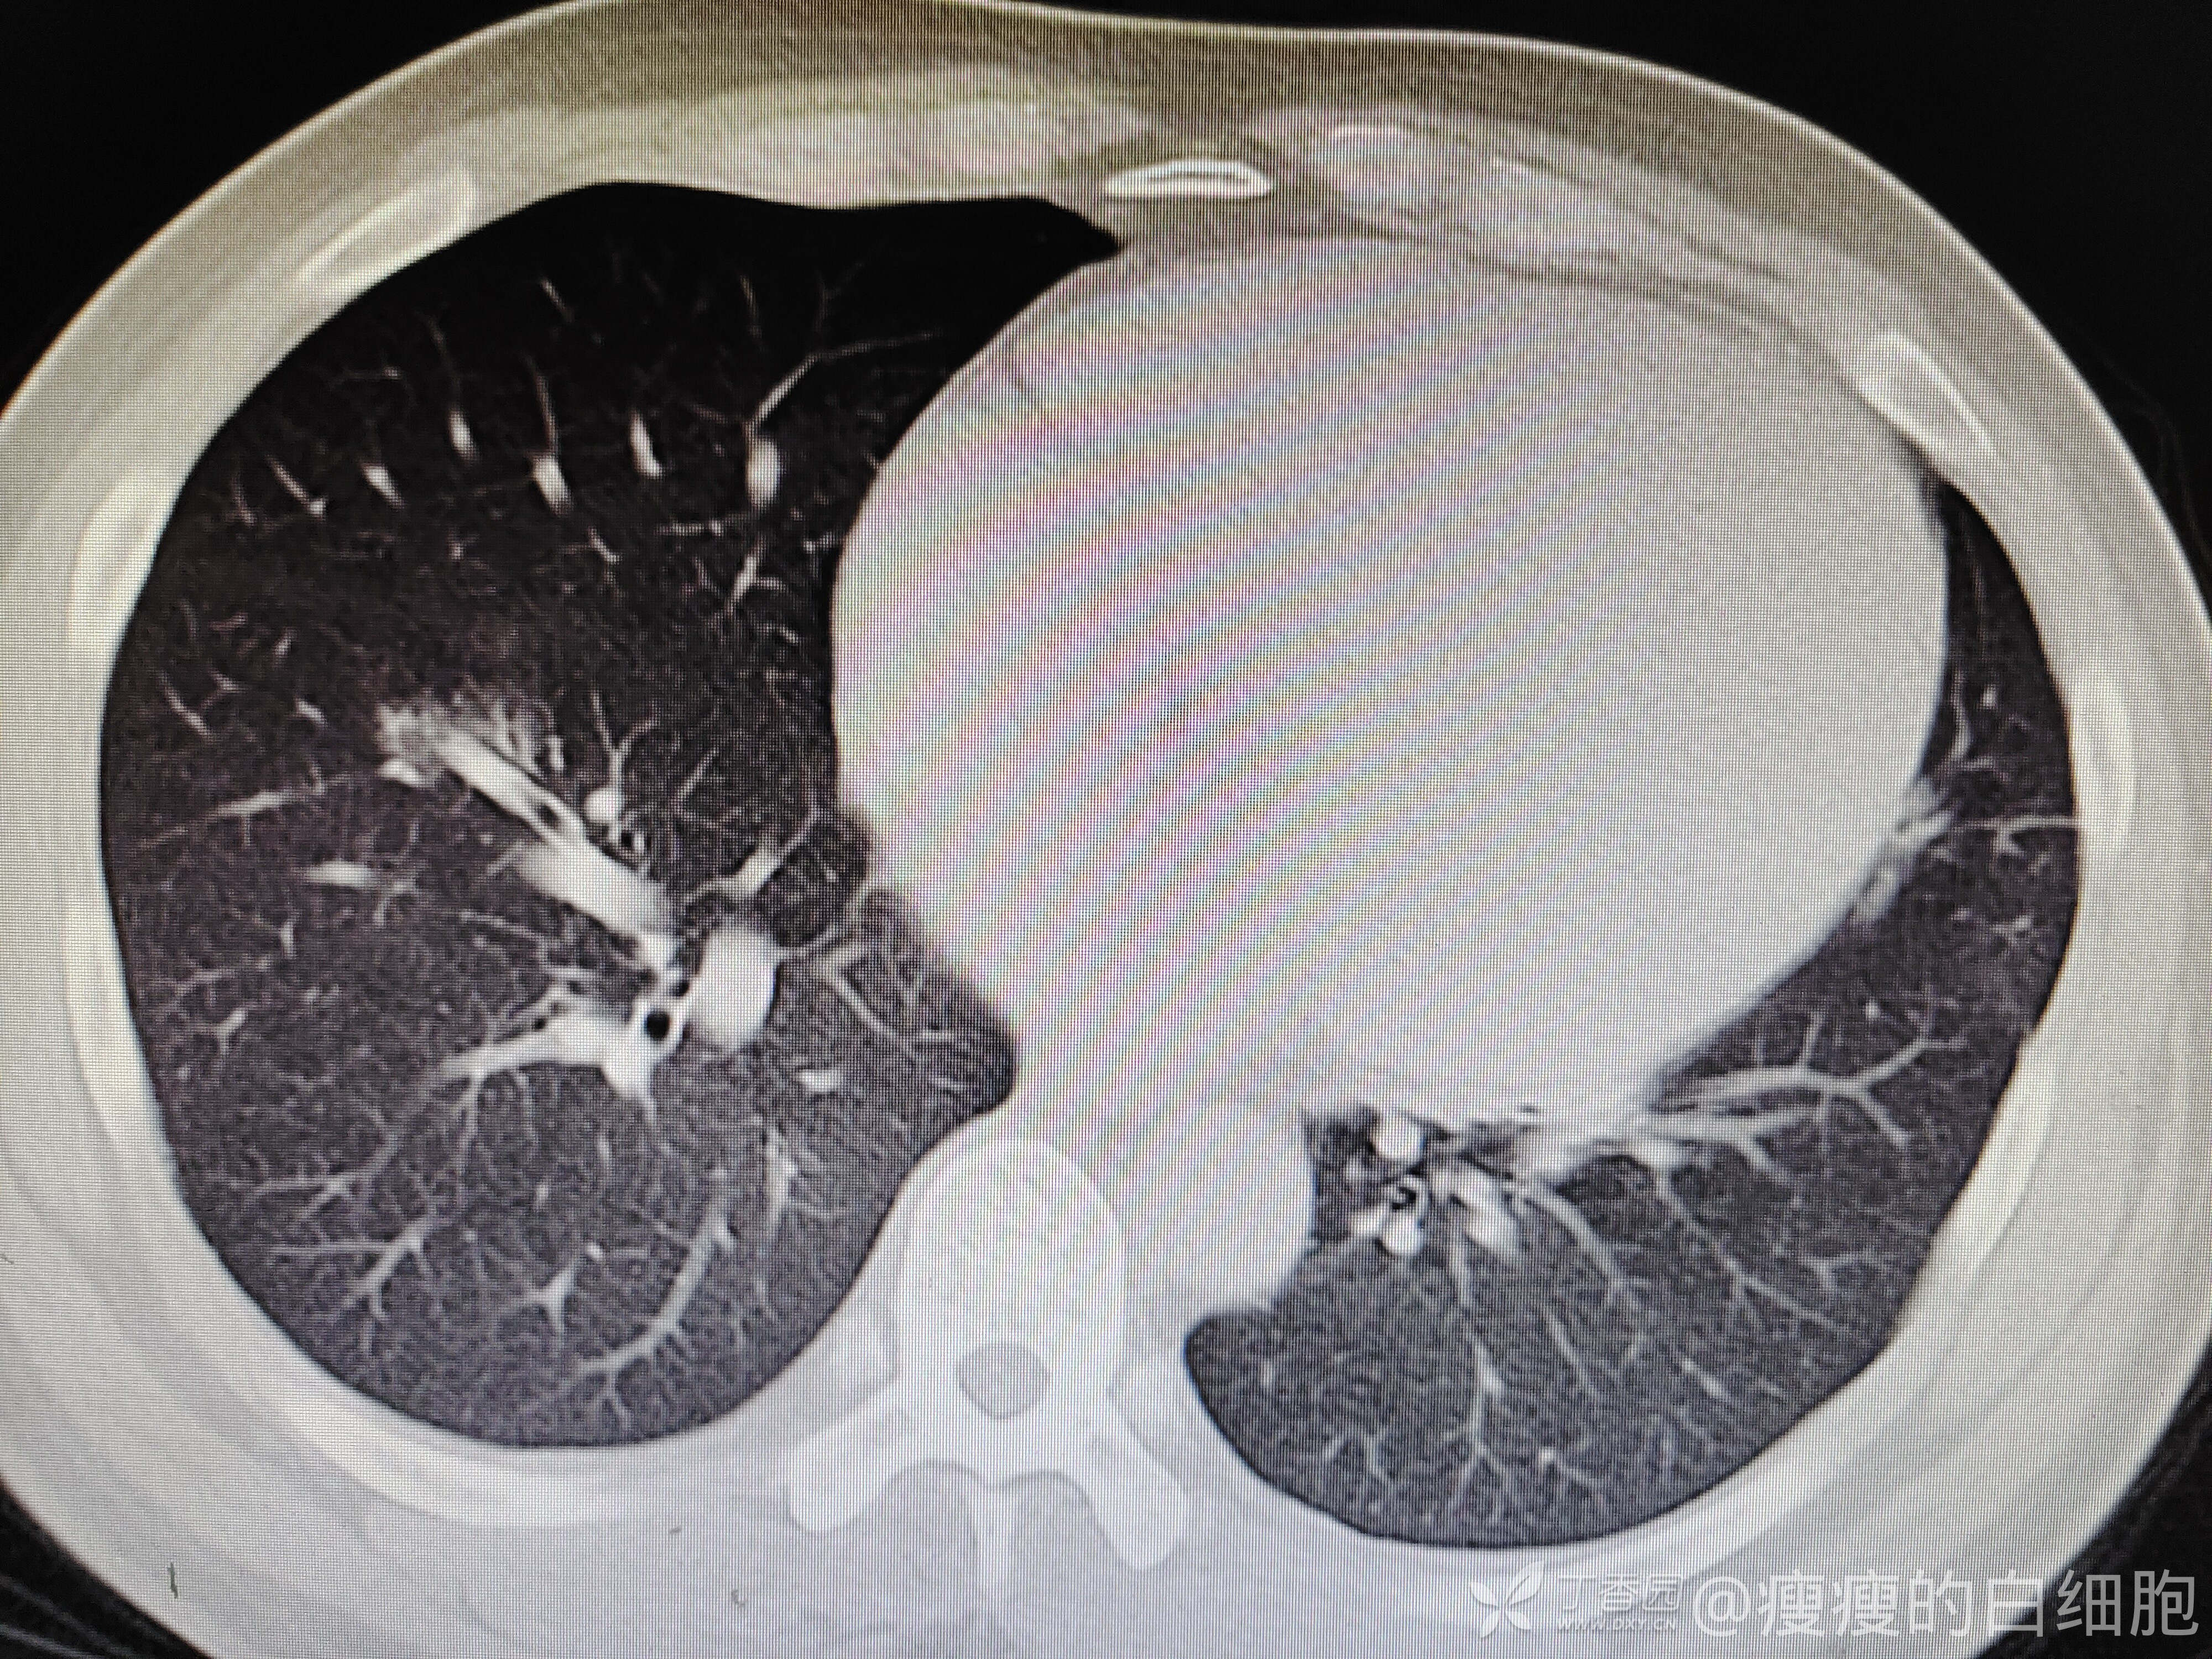

西门开心 推荐男子,35岁,因为咳嗽半月来诊,门诊抗感染治疗5天。既往有高血压病史,未治疗,入院时血常规及胸部CT如下

5天后咳嗽略减轻,但感胸闷。这时候血压达到了169/126mmhg,查体肺部无干湿性啰音,下肢也无水肿。再次复查胸部CT